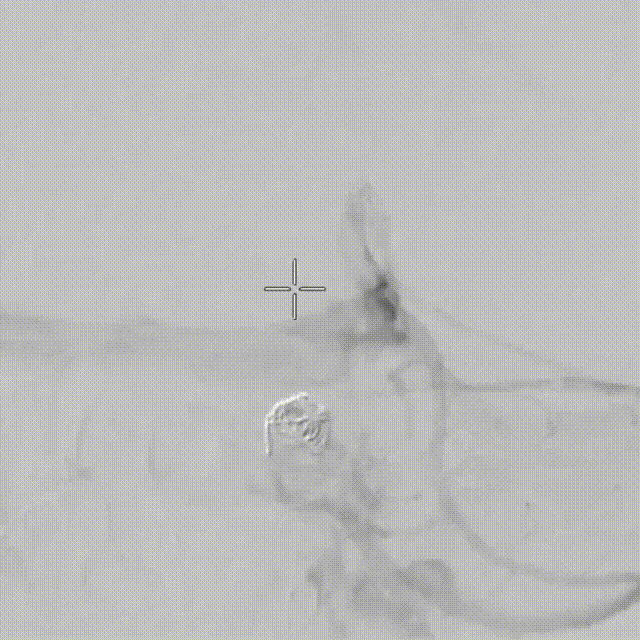

Tubridge Plus Case 2